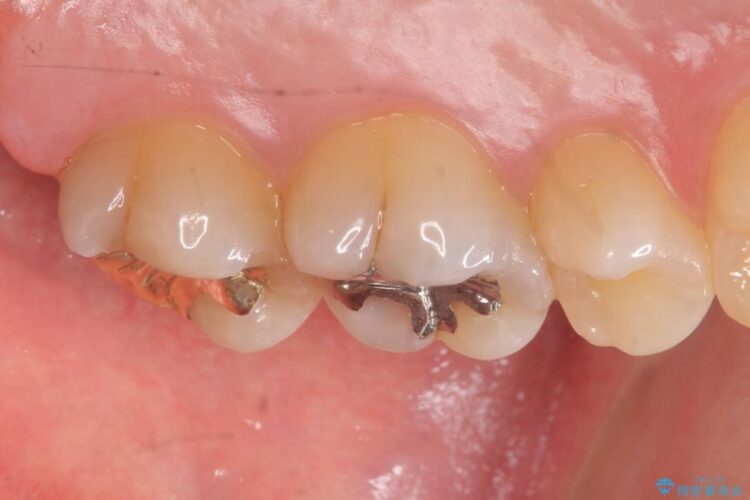

治療後について

虫歯が進行して歯が欠けてしまう前に早期発見・治療をすることが重要です。初期の虫歯は痛みも少なく短期間での治療が可能ですので、定期的に検診などを受けることをおすすめいたします。

ゴールドインレーはセラミックより強度高く、使用される金合金や白金加金は汚れの付きにくいという特徴を持っており、耐用年数が長いことが特徴としてあります。特に奥歯など強く力が欠けられる箇所に適しています。

反対にデメリットして金属であるため審美性に欠けるという点があります。